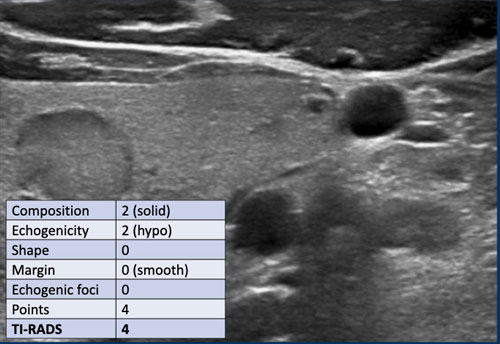

Trường hợp 2

Quan sát hình ảnh và xác định điểm TI-RADS.

Cuộn hình ảnh để xem điểm TI-RADS.

Nốt này giảm âm so với mô tuyến giáp bình thường có thể nhìn thấy ở mặt bụng của nốt.

Điểm TI-RADS: 2 điểm cho độ hồi âm giảm âm.